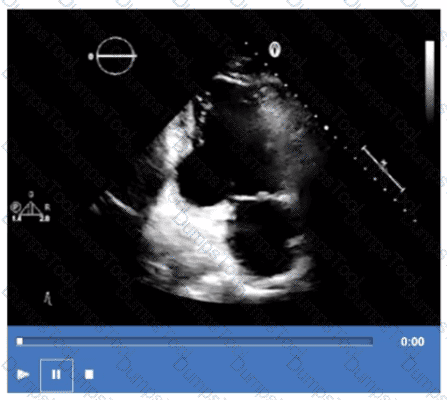

What is the regional wall motion assessment of the two-chamber view displayed in this video?